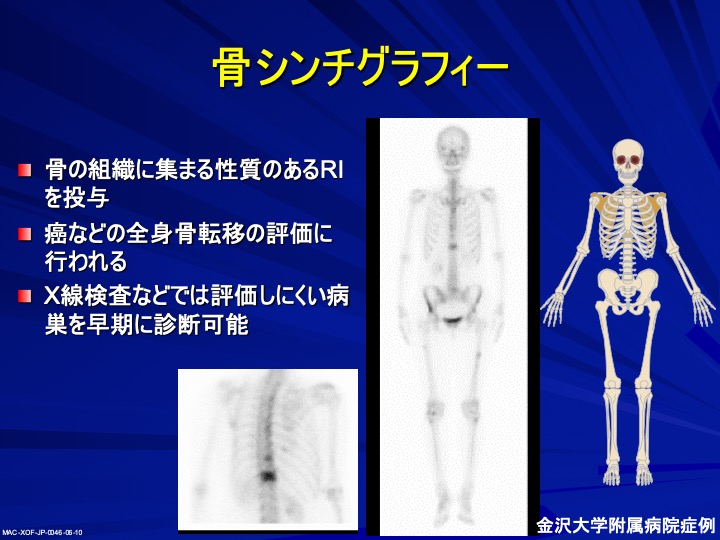

前立腺がんの検査 骨シンチグラフィー 前立腺がんの治療と名医

主な核医学検査 骨 骨シンチグラフィ 核医学検査のご案内 医療関係者

骨シンチグラフィーとは 佐賀大学病院放射線科アンオフィシャル

前立腺がんの検査 画像検査 Ct Mri 骨シンチグラフィ で何がわかる

骨シンチグラフィによる骨転移の診断 Bone Scan Ct Mri画像診断